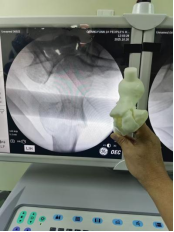

案例2:患者,88岁高龄,因摔伤致右髋关节疼痛伴活动受限3小时入院。入院诊断:右股骨粗隆间粉碎性骨折、重度骨质疏松。鉴于高龄骨质疏松粉碎性骨折对髓内钉力线与螺旋刀片锚定的严苛要求,科室以3D打印1:1骨折模型提供“实体沙盘”,助力医生反复进行骨折复位演练,精确测量进针点、主钉长度、前倾角及螺旋刀片深度精,评估复位稳定性,最后成功完成3D打印模型辅助下行粗隆间骨折PFNA闭合复位内固定术,保障了手术安全与效果。

(术中)